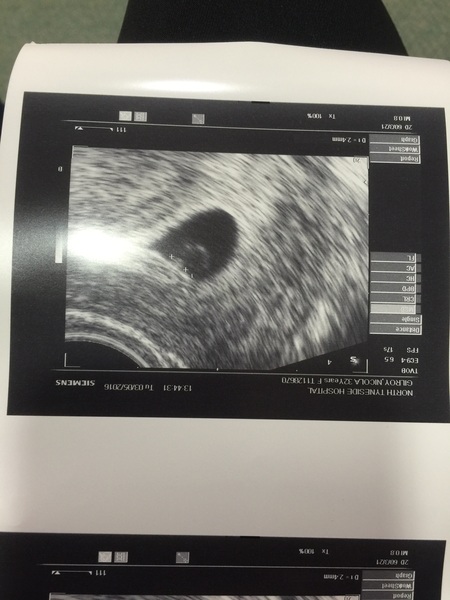

Hi I had a scan on Tuesday they said I'm less than 6 weeks they found a heartbeat a tiny white flicker so think I'm about 5 weeks. No idea when I'm due can't work out if it's late December or early January. According to last day of period it's late December but given scan dated me less than 6 weeks I think it's like to be early January. Today I've been having a few cramps don't know if that's normal. I was so ill in my last pregnancy found out 6-7 weeks but although I've been tired and feel sick if I don't eat every so often I'm doing ok. Sometimes major headaches.

The heartbeat is between the 2 crosses.